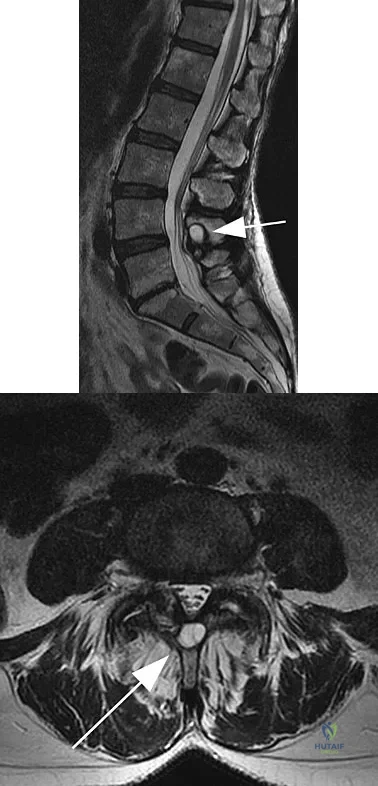

Question 93 High Yield

Figures 11a and 11b show the T2-weighted MRI scans of the lumbar spine of a 53-year-old woman who has low back and right lower extremity pain. What structure is the arrow pointing to in Figure 11a?

Detailed Explanation